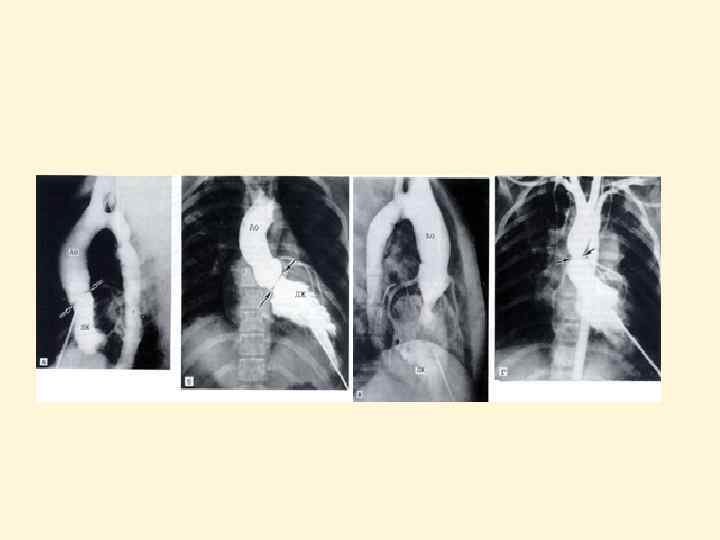

МРТ при аортальной недостаточности (стрелка указывает струю регургитации)

МРТ грудной клетки. Аневризма восходящего отдела аорты Ао Ао